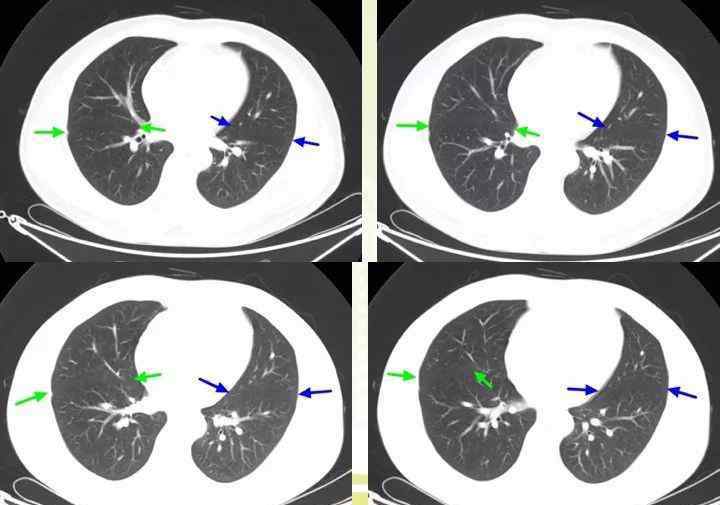

今天丁香园论坛的图像专家@华夏蓝雄来讲解:胸部CT断层解剖,带你从头开始读CT。